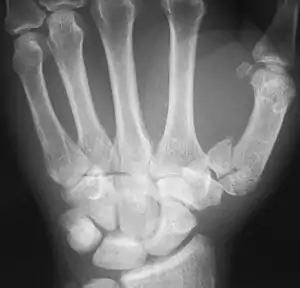

Fracture of the first metacarpal (Rolando's fracture).